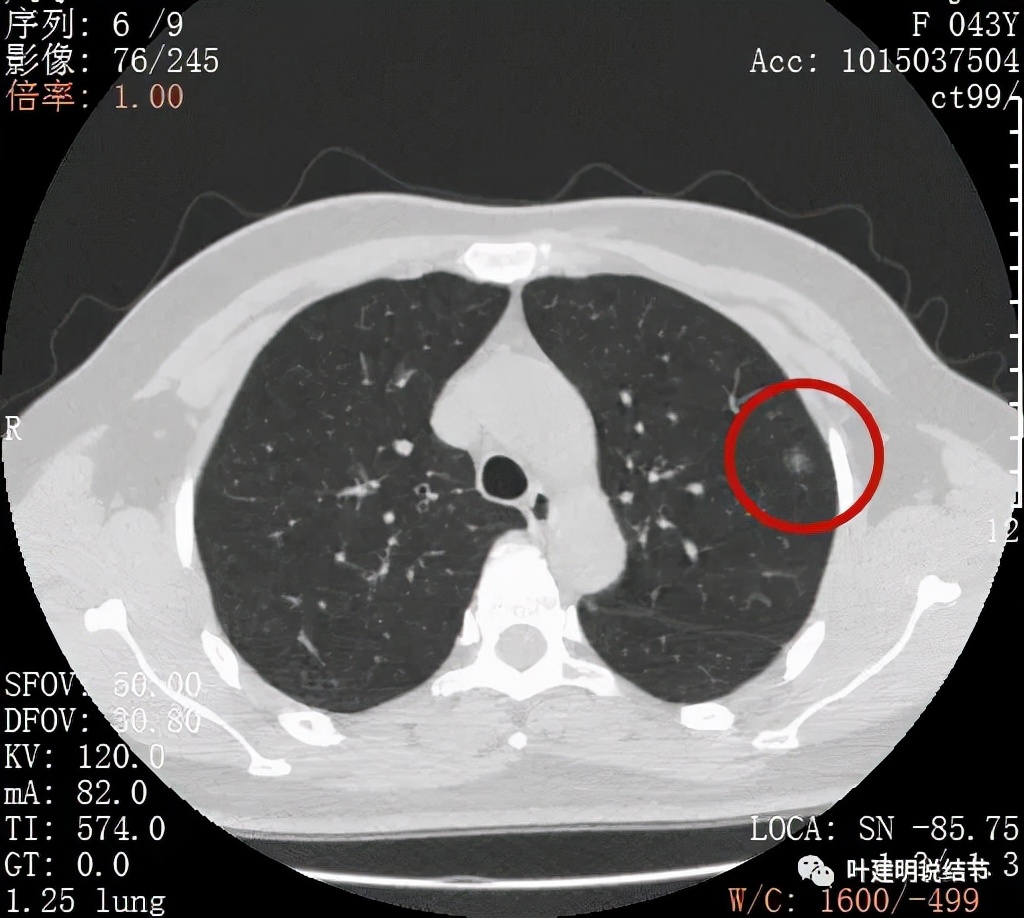

上图显示混合磨玻璃结节,中间点状高密度区域,边上有微小血管征

上图示病灶边缘磨玻璃成分有的区域密度过低(绿色箭头),事后回头来看,磨玻璃部分的密度过低,不容易是浸润性腺癌,而更符合原位腺癌

上图示瘤肺边界处显模糊(砖色箭头),病灶内部仍是有偏高密度的点状成分

上图层面也显示病灶边缘欠清,有些模糊,虽总体轮廓还是比较清晰

从以上靶扫描图像上看,给人的印象是肿瘤范畴的结节,是混合磨玻璃结节,但磨玻璃部分的密度偏低,有的边缘显模糊,中间有点状高密度,也有微小血管进入,应该至少微浸润性腺癌可能性大。持续存在已经2月余,位置又还靠边上的,可考虑手术切除。下面再来瞧瞧后处理重建的图像: